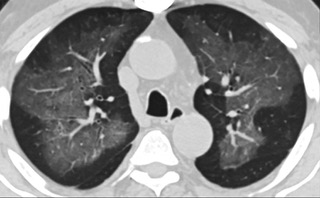

疑點(diǎn)二,中國(guó)科研工作者從60篇研究論文中篩選出142位電子煙肺炎患者的250張影像圖片,邀請(qǐng)3位放射科權(quán)威專家,對(duì)上述全部影像圖片、相關(guān)病人臨床信息以及文獻(xiàn)原文進(jìn)行了仔細(xì)全面研究與審查,又有了新的發(fā)現(xiàn)。

6天后的軸向CT平掃圖像顯示毛玻璃影變?yōu)閷?shí)變和輕度結(jié)構(gòu)扭曲。(同一病人CT影像)

16位被文獻(xiàn)報(bào)道為電子煙肺炎的患者被專家判定為“病毒性感染”,即有可能是新冠肺炎的“疑診患者”,其中更有5位臨床癥狀和治療情況相對(duì)完整的患者被判定為“中度可疑”。因此在2019年美國(guó)報(bào)道的電子煙肺炎中存在病毒性感染的病例,而且不排除美國(guó)電子煙肺炎中存在新冠肺炎的可能性。